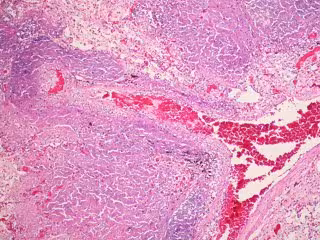

Archivo - Tuberculosis

Archivo - Tuberculosis - FLICKER/ PULMONARY PATHOLOGY - Archivo